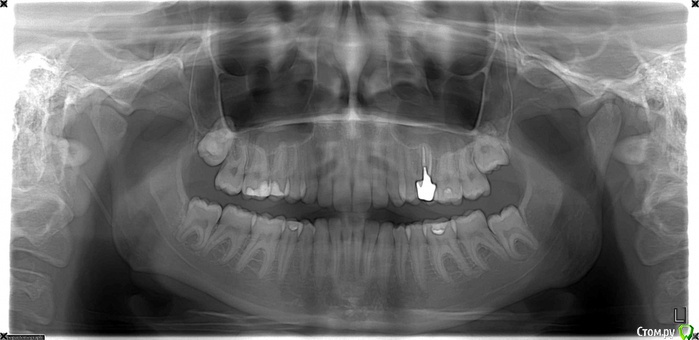

Laaeer Опубликовано 17 сентября, 2015 Поделиться Опубликовано 17 сентября, 2015 (изменено) Добрый день! Несмотря на большое количество подобных тем, хочется открыть и свою, так как, конечно, всё не как у других . Что было до: 24 года, симпатичное лицо с некрасивой улыбкой (зубы наклонены внутрь, глубокий дистальный прикус, сзчла). Небольшая ассиметрия, компенсированный прикус. Щелчки в суставе справа и редкие тянущие слабые боли, стираемость клыка справа и зуба прямо под ним. Эту ситуацию я наивно полагала исправить брекет-системой, ортодонт в ответ на жалобы на щелчки и стираемость сообщил, что щелчки останутся, а стираемость бывает у всех. И вообще был оптимистичен, сказав что ситуация - фигня и нечего особо делать. Брекеты были поставлены (к настоящему моменту я относила их 7 мес), после 6 мес. и выравнивания зубных рядов поставлены самые тугие резинки от нижней семерки к верхней тройке, которые должны были сместить челюсть вперед и вытянуть глубоко посаженные задние зубы. Зубы, только развернувшиеся по красивой дуге стали обратно тянуться в "крысиную улыбку", заворачиваться внутрь. Приношении резинок полностью прошли все боли. С этим я пошла к хирургу. Пластических операций не боюсь, цель - убрать ассиметрию, убрать щелчки, выдвинуть подбородок (улучшить профиль), улучшить эстетику улыбки. Хирург-ортодонт сказал, чтобы я прекратила заниматься ерундой: недоразвитие нижней челюсти брекетами не исправить. Резинки в некоторой степени помогут поднять прикус, но при этом верхние зубы "завернутся", при этом скорее всего хороших контактов зубов добиться не удастся. И все мои время и деньги потрачены, фактически, на небольшой подъем прикуса. Что сустав загружен и работает на износ.Предложенное хирургом лечение: отменить резинки, выровнять до конца зубные ряды, затем хир. выдвижение НЧ, добавление фрагмента на ВЧ (чтобы убрать ассиметрию, кривую улыбку). Потом еще 6 мес брекетов. Это значительно улучшит эстетику и разгрузит сустав. В квалификации хирурга сомневаться не приходится, а в орте есть всё-таки сомнения, но хирургу-то за операции деньги платят так что хочу спросить уважаемых участников форума, кто же из докторов прав? И могут ли быть у такой операции серьезные последствия? Мне она представлена как безопасная, зубы фиксированы брекетами, челюсти - титановыми пластинами, все прогнозируется, всё очень хорошо. (То, что реабилитация тяжелая, я знаю и готова к этому, но вдруг есть какие-то риски, о которых мне не сказали?). Сейчас сняла резинки, беспокоят редкие стреляющие боли в суставе и частые головные боли, начинаются от виска и затем боль распространяется. Боли сильнее, чем до брекетов. Стираемость исчезла. Изменено 17 сентября, 2015 пользователем Laaeer Ссылка на комментарий

Laaeer Опубликовано 17 сентября, 2015 Автор Поделиться Опубликовано 17 сентября, 2015 (изменено) http://img0.liveinternet.ru/images/attach/c/7/125/79/125079440_1175715_mrt.jpghttp://s020.radikal.ru/i700/1509/d1/992519e3c10f.jpg Изменено 17 сентября, 2015 пользователем Laaeer Ссылка на комментарий

Laaeer Опубликовано 7 октября, 2015 Автор Поделиться Опубликовано 7 октября, 2015 (изменено) По результатам осмотра и консультации в Мечникова (были еще и другие, но мнению завкафедры этого заведения нельзя не доверять) буду делать двухчелюстную остеотомию. Глубокий дистальный травмирующий прикус. Работать с суставом будем после нормализации положения и размера челюстей. Еще раз спасибо за комментарии. Если это читает мой хирург - нет, я не жалею, что оббегала пол города и опросила кучу людей, включая этот форум, теперь я могу вам полностью доверять Тему можно закрыть. Изменено 7 октября, 2015 пользователем Laaeer Ссылка на комментарий